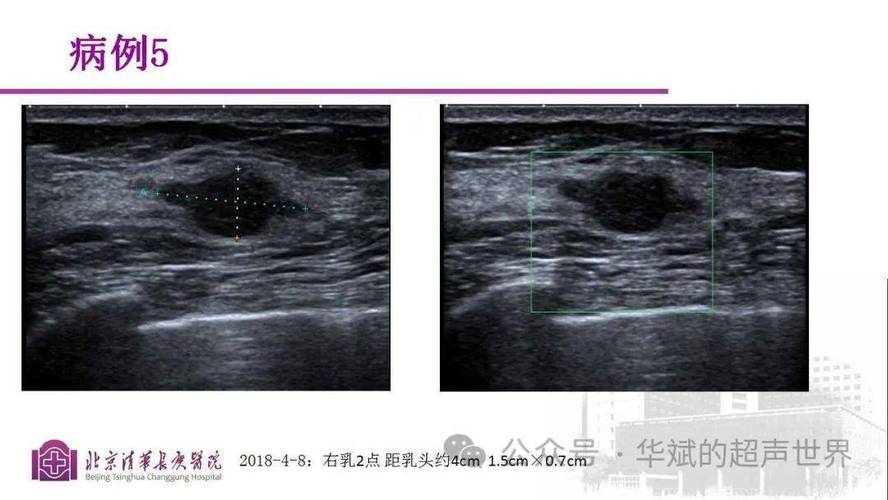

超声引导下的介入诊断与治疗

超声引导下穿刺活检是乳腺病灶定性诊断的金标准,其具有实时、精准、并发症少等优势,超声引导下微波消融、射频消融等微创技术为早期乳腺癌患者提供了保乳治疗的新选择,Li等(2025)的研究表明,对于直径≤2cm的乳腺癌,超声消融的局部控制率与手术相当,且患者生活质量显著改善。